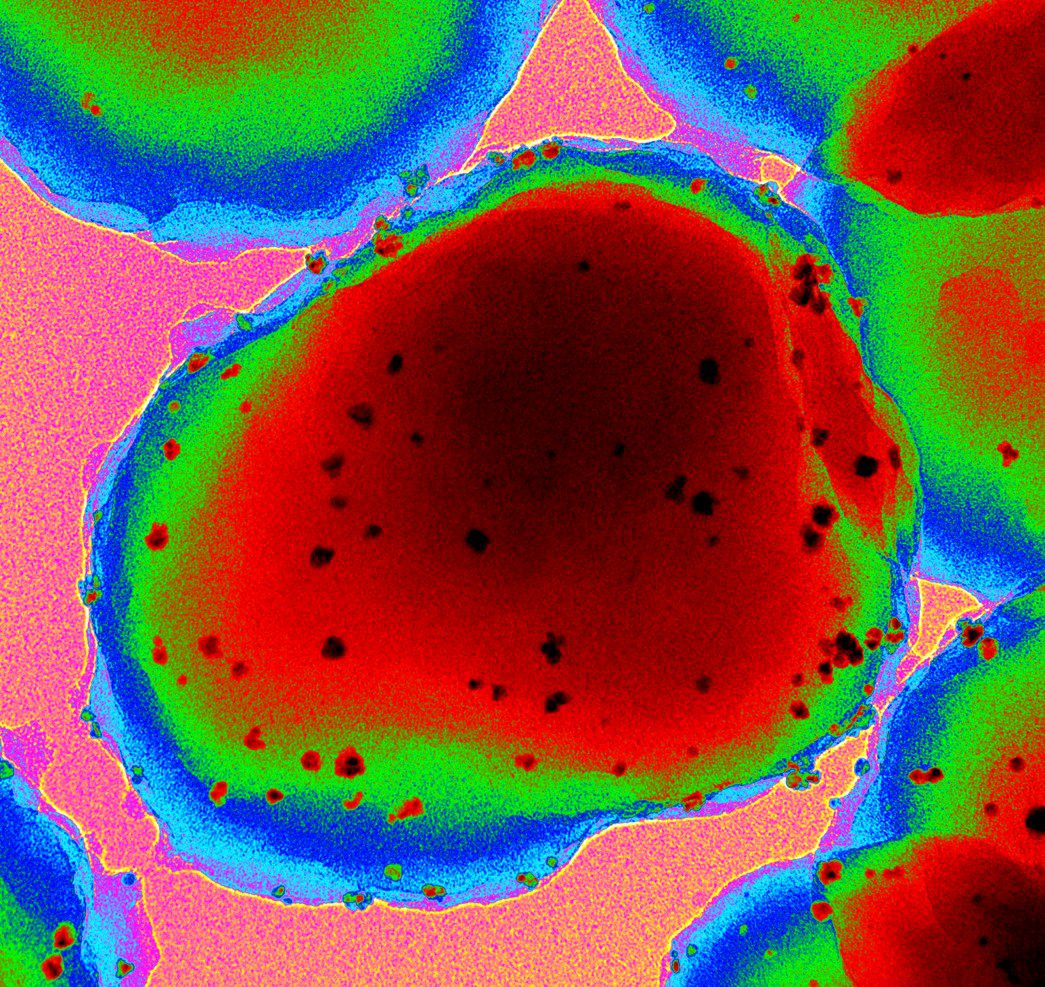

Research at the Pfizer-University of Granada-Junta de Andalucía Centre for Genomics and Oncology Research (GENYO) is organised into two main areas: Functional Genomics, which corresponds to the basic area, and Personalised Medicine, focused on clinical applications. These areas are structured into strategic lines. The Functional Genomics area focuses on the study of the human genome and cancer genomics, addressing the fundamental mechanisms of genetic and molecular biology. The area of Personalised Medicine focuses on the detection, diagnosis, monitoring and prognosis of diseases, as well as the design and implementation of advanced therapies, with the aim of translating scientific knowledge into personalised solutions for patients. This structure allows GENyO to integrate basic and applied research, driving significant advances in the field of genomics and oncology.